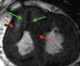

Subvalvular left ventricular aneurysm

Hypertrophic cardiomyopathy (HCM) is a condition in which the heart becomes thickened without an obvious cause. The parts of the heart most commonly affected are the interventricular septum and the ventricles. [Source: Wikipedia ]